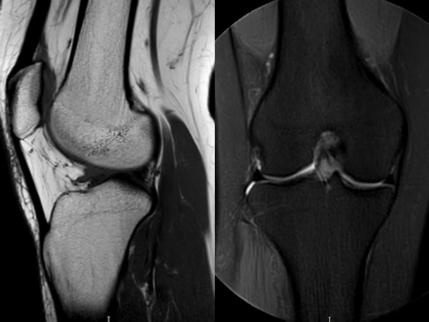

3. 上下楼“针刺痛”——软骨的“磨砂纸预警”

场景:爬楼梯时膝盖刺痛,久坐后僵硬如“生锈齿轮”

MRI侦查:发现软骨变薄、缺损(早期骨关节炎信号),赶在“路面塌方”前修复

(软骨损伤)